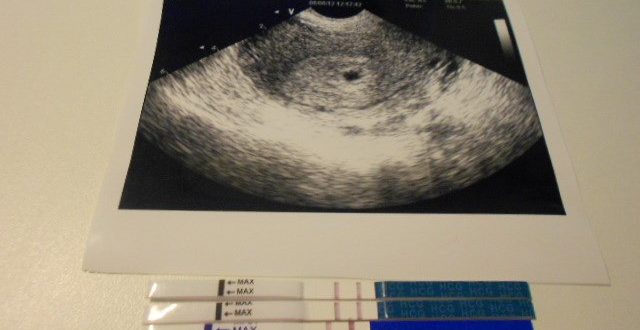

УЗИ через неделю после зачатия

На каком сроке узи показывает беременность? «На каком сроке УЗИ показывает беременность?» — это самый главный и волнующий вопрос для женщин. Возникает он в случае задержки менструации или…

УЗИ для исключения внематочной беременности

Можно ли увидеть внематочную беременность на УЗИ Внематочная беременность — это патологическая беременность, которая представляет собой серьезную угрозу здоровью женщины и требует неотложной медицинской помощи. Оплодотворенная яйцеклетка в…